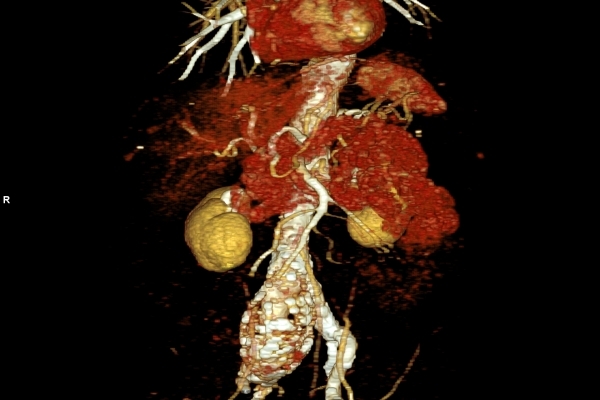

• Gefäßdiagnostik (CT-Angiographie)

Wir bieten ein breites Spektrum an Untersuchungen an, von Standarduntersuchungen der Gelenke, Organe oder großflächigen Körperregionen bis zu Spezialuntersuchungen zum Beispiel des Herzen oder der Gefäße. Zusätzlich werden Angiographien (Darstellung von Blutgefäßen), Endometriose-Abklärungen und Mamma-Untersuchungen durchgeführt. Genauere Details können Sie der MRT/CT-Übersicht und der Preisliste entnehmen, oder Sie wenden sich direkt an unser Team, das Sie gerne zur passenden Untersuchung berät.